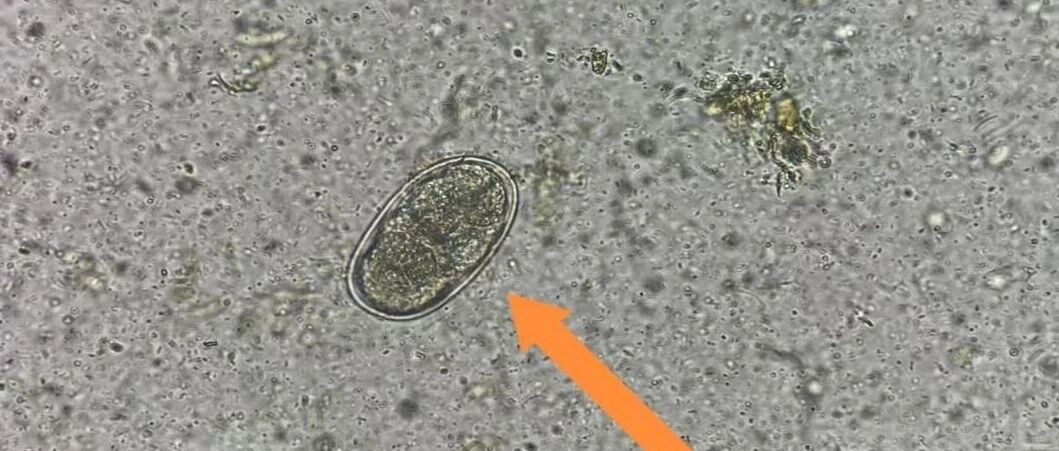

日产卵上万枚!它在肠道里“偷血”,难怪长期贫血 健康杭州 · 公众号 · · 8 月前 · |